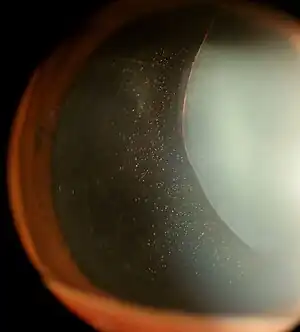

Anterior lens luxation with cataract formation in a cat